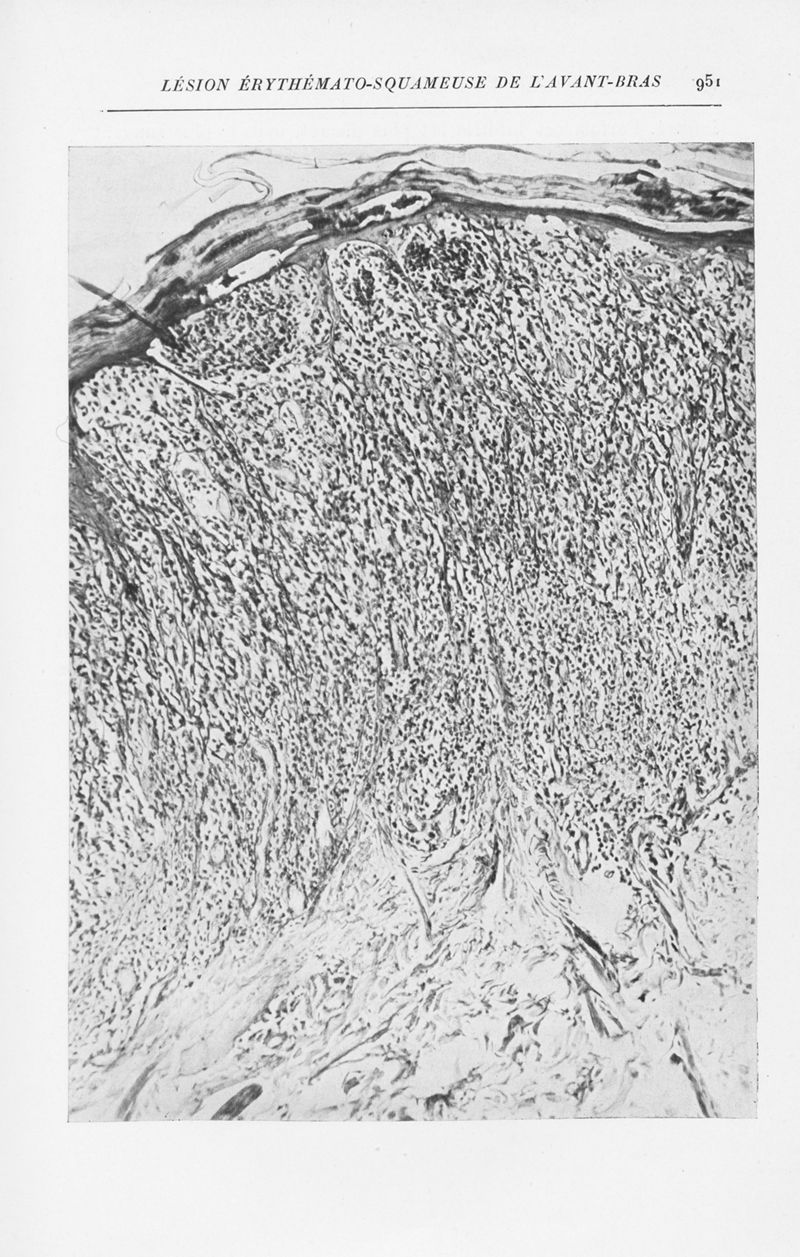

Annales de dermatologie et de syphiligraphie

7ème série, tome X. - Paris : Masson, 1939-1940.